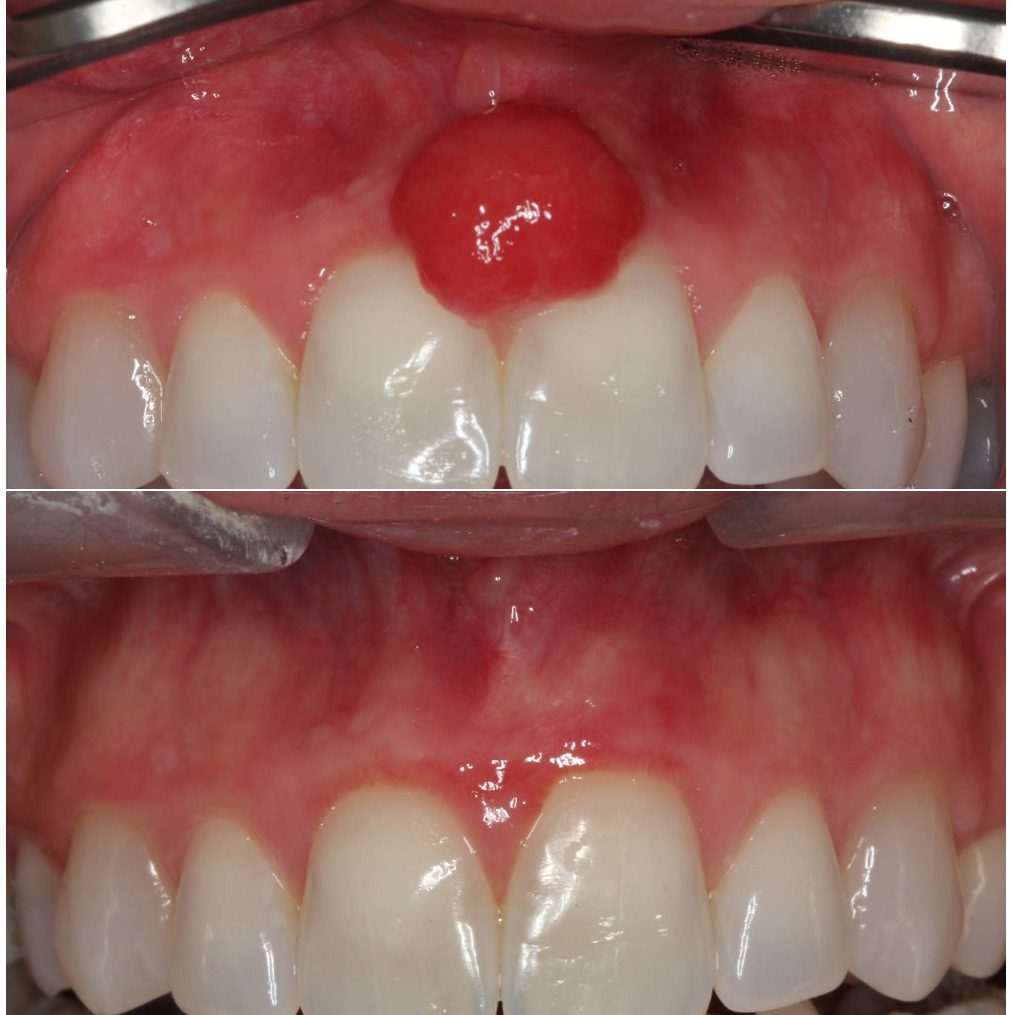

Laser was used to dissect the tumor and maintain the architecture with our damaging the gum around the teeth